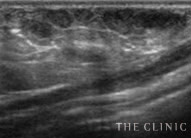

吸引・除去後

しこりの消失を確認 -

除去したヒアルロン酸

目視することで確実に除去